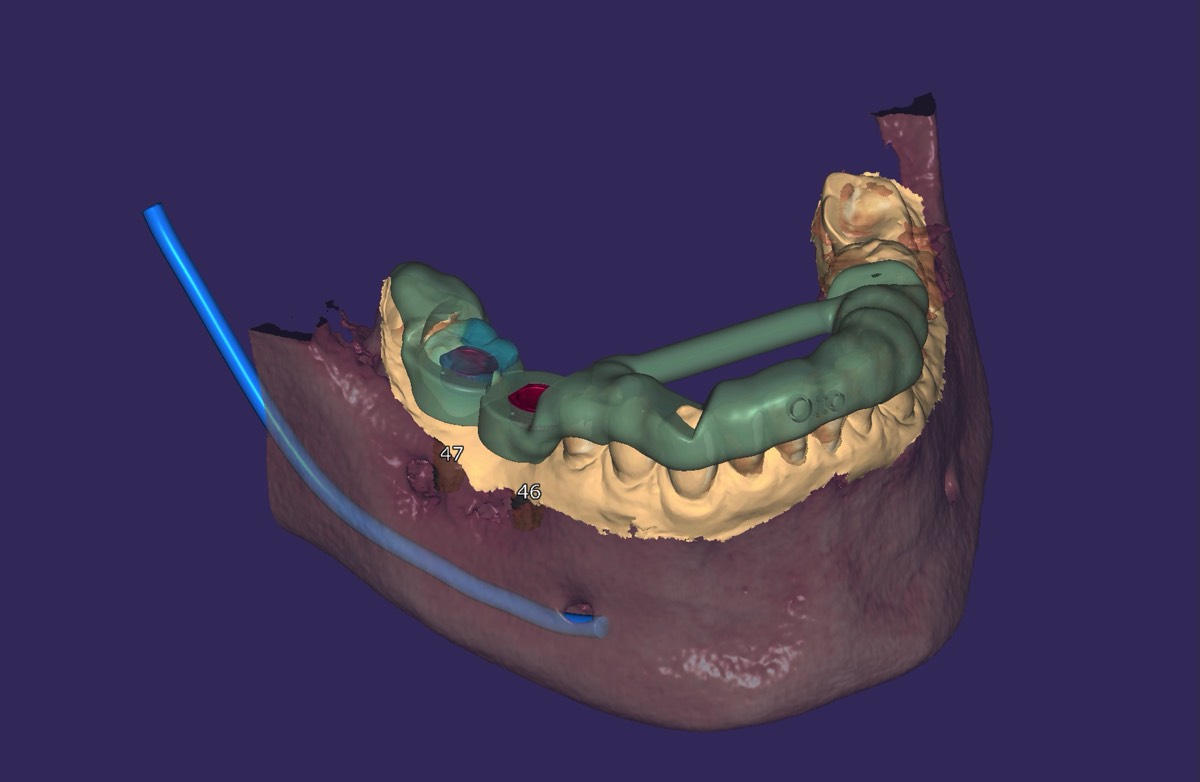

Implantologie

Falls ein Zahn trotz aller Bemühungen nicht erhalten werden kann, bieten sich Implantate als Substanz schon in der Ersatz an. Ein Implantat ist eine künstliche Zahnwurzel, die im Kieferknochen verankert wird. Darauf lässt sich eine Krone befestigen, mit der man wie auf einem natürlichen Zahn kauen kann. Somit kann das Abschleifen von gesunden Zähnen, z. B. für eine Brücke vermieden werden. Durch den Einsatz von dreidimensional Röntgen (DVT) wird eine besonders präzise Implantatsetzung ermöglicht. Man Kann vor der OP den Knochen vermessen und die Lage der Implantate digital planen.